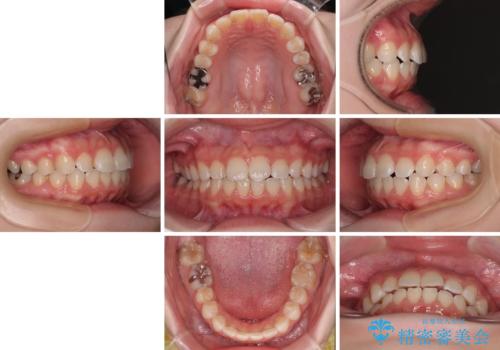

- 上下前歯部のデコボコを気にして来院された患者様です。

叢生は軽度であったため、マウスピースでもワイヤー装置でも対応可能でしたが、マウスピースを長時間使用する自信がないとのことでワイヤー装置にて矯正治療を行うこととしました。

叢生が軽度であったため、僅か半年で装置を除去することができました。